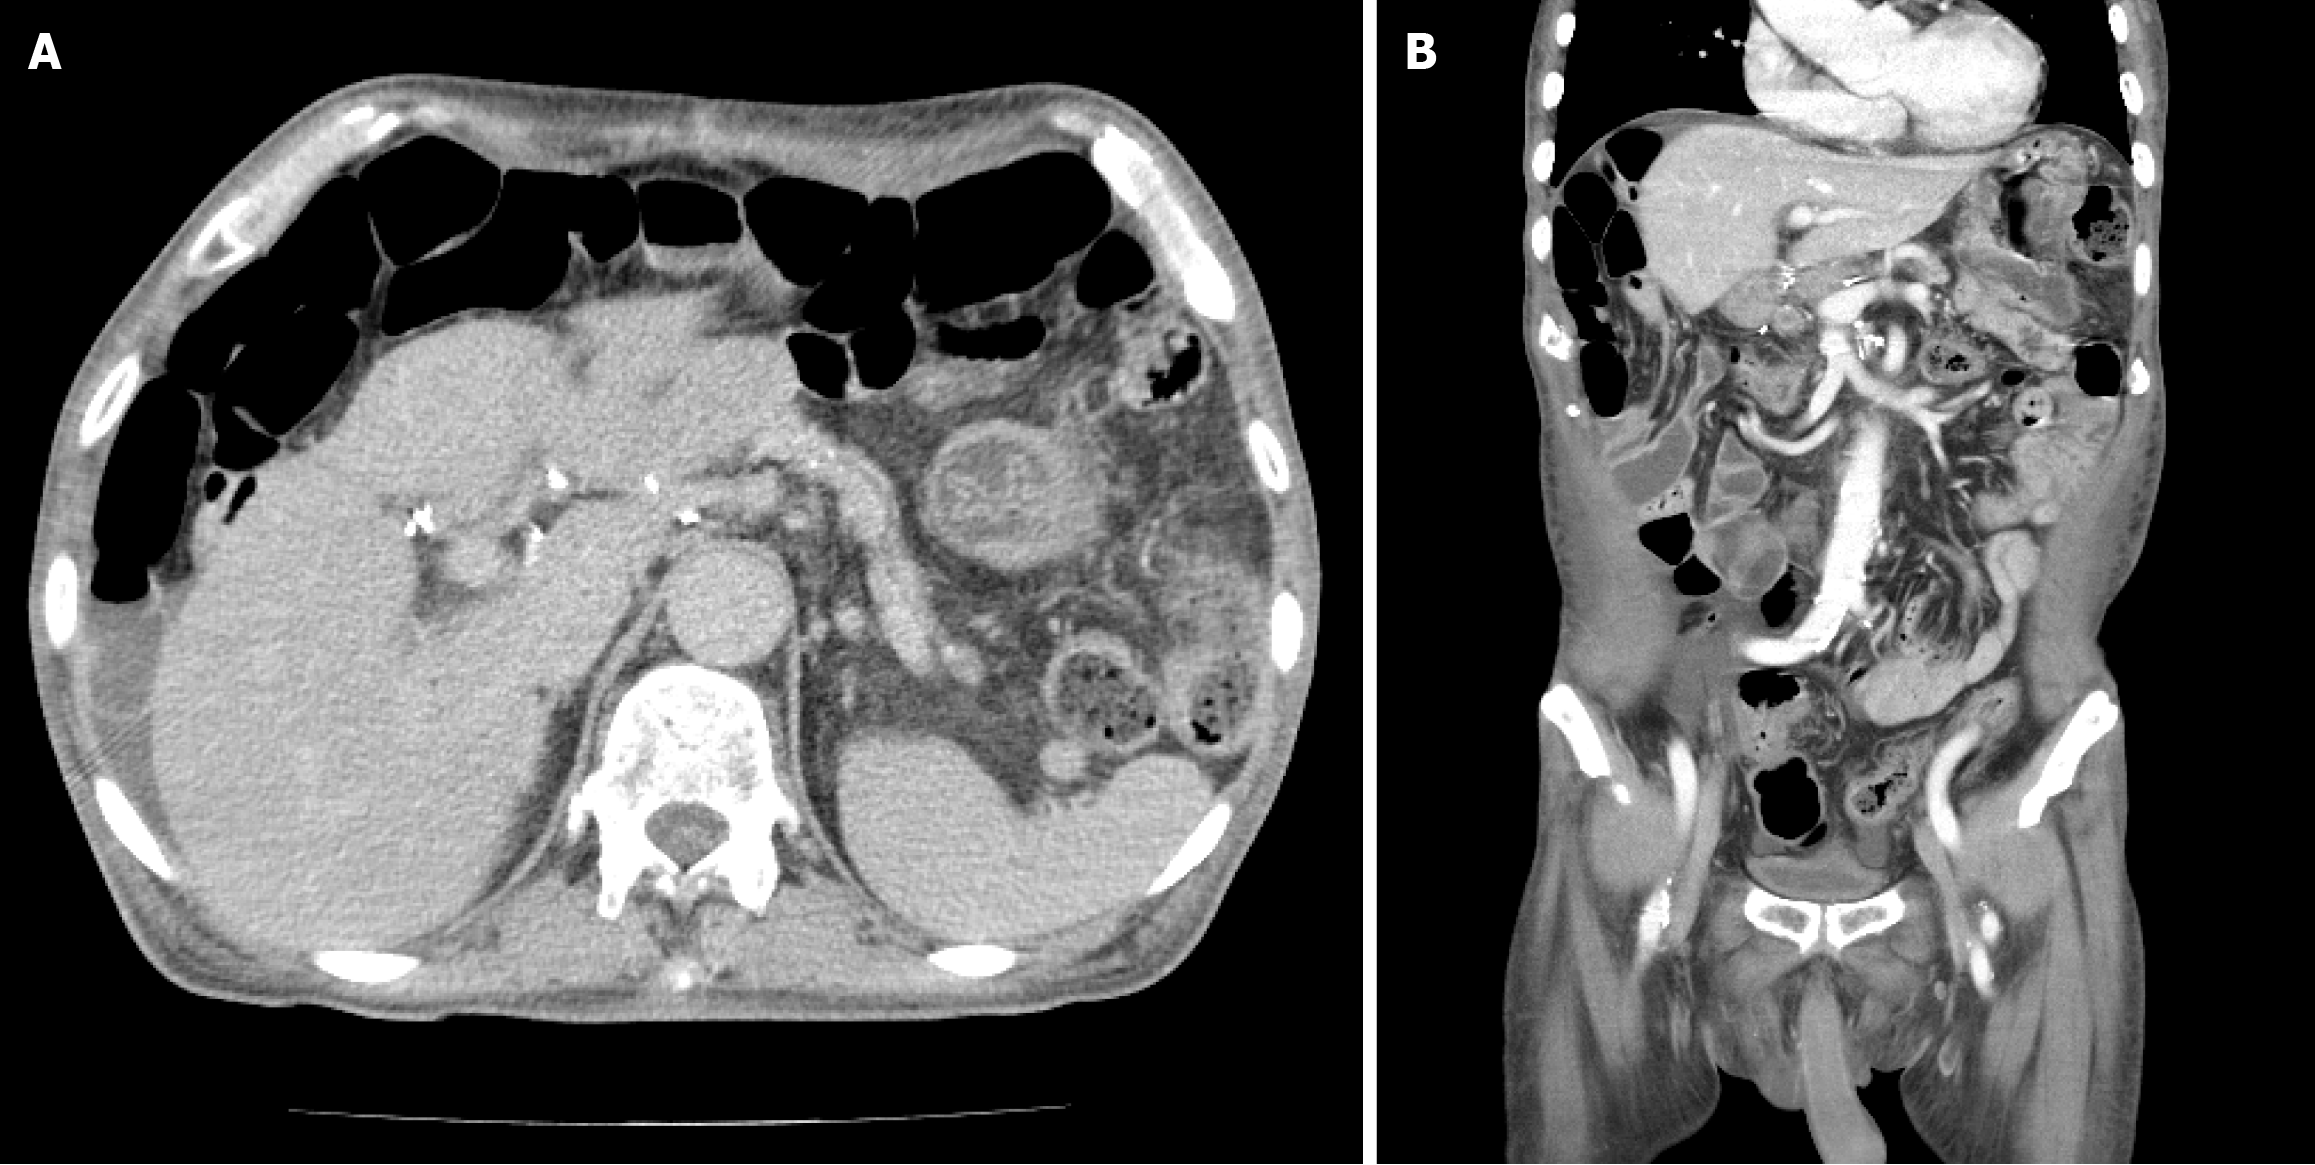

Figure 6 One-year follow-up abdominal contrast-enhanced computed tomography after pancreaticoduodenectomy.

The images demonstrate postoperative anatomical changes without evidence of surgical complications such as anastomotic leakage or intra-abdominal abscess. However, after the patient resumed alcohol consumption, the computed tomography revealed a perihepatic fluid collection in the perihepatic space. A: Axial view; B: Coronal view.